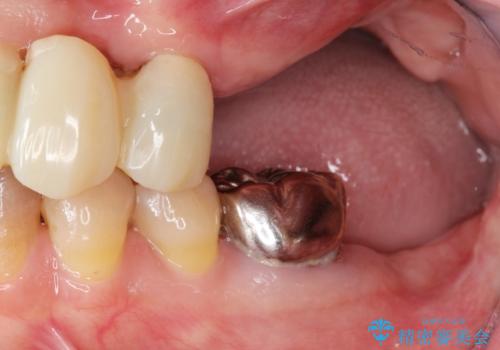

- 他院で上顎は全て抜歯し、入れ歯にする必要があると言われ相談に来院されました。

検査の結果、重度の歯周病であることから保存が難しい歯は抜歯を行いインプラントを、残すことが可能な歯には再生治療を含めた歯周病治療を行いより多くの歯を残す歯周病治療を計画します。

上顎は、残っている前歯も揺れがあり残すためにはクラウンでつなぐ歯周補綴が必要な状態です。

また咬合負担に不安のある前歯を助けるためにも、臼歯部にインプラント補綴を行いしっかりとかめる状態とすることも大切です。